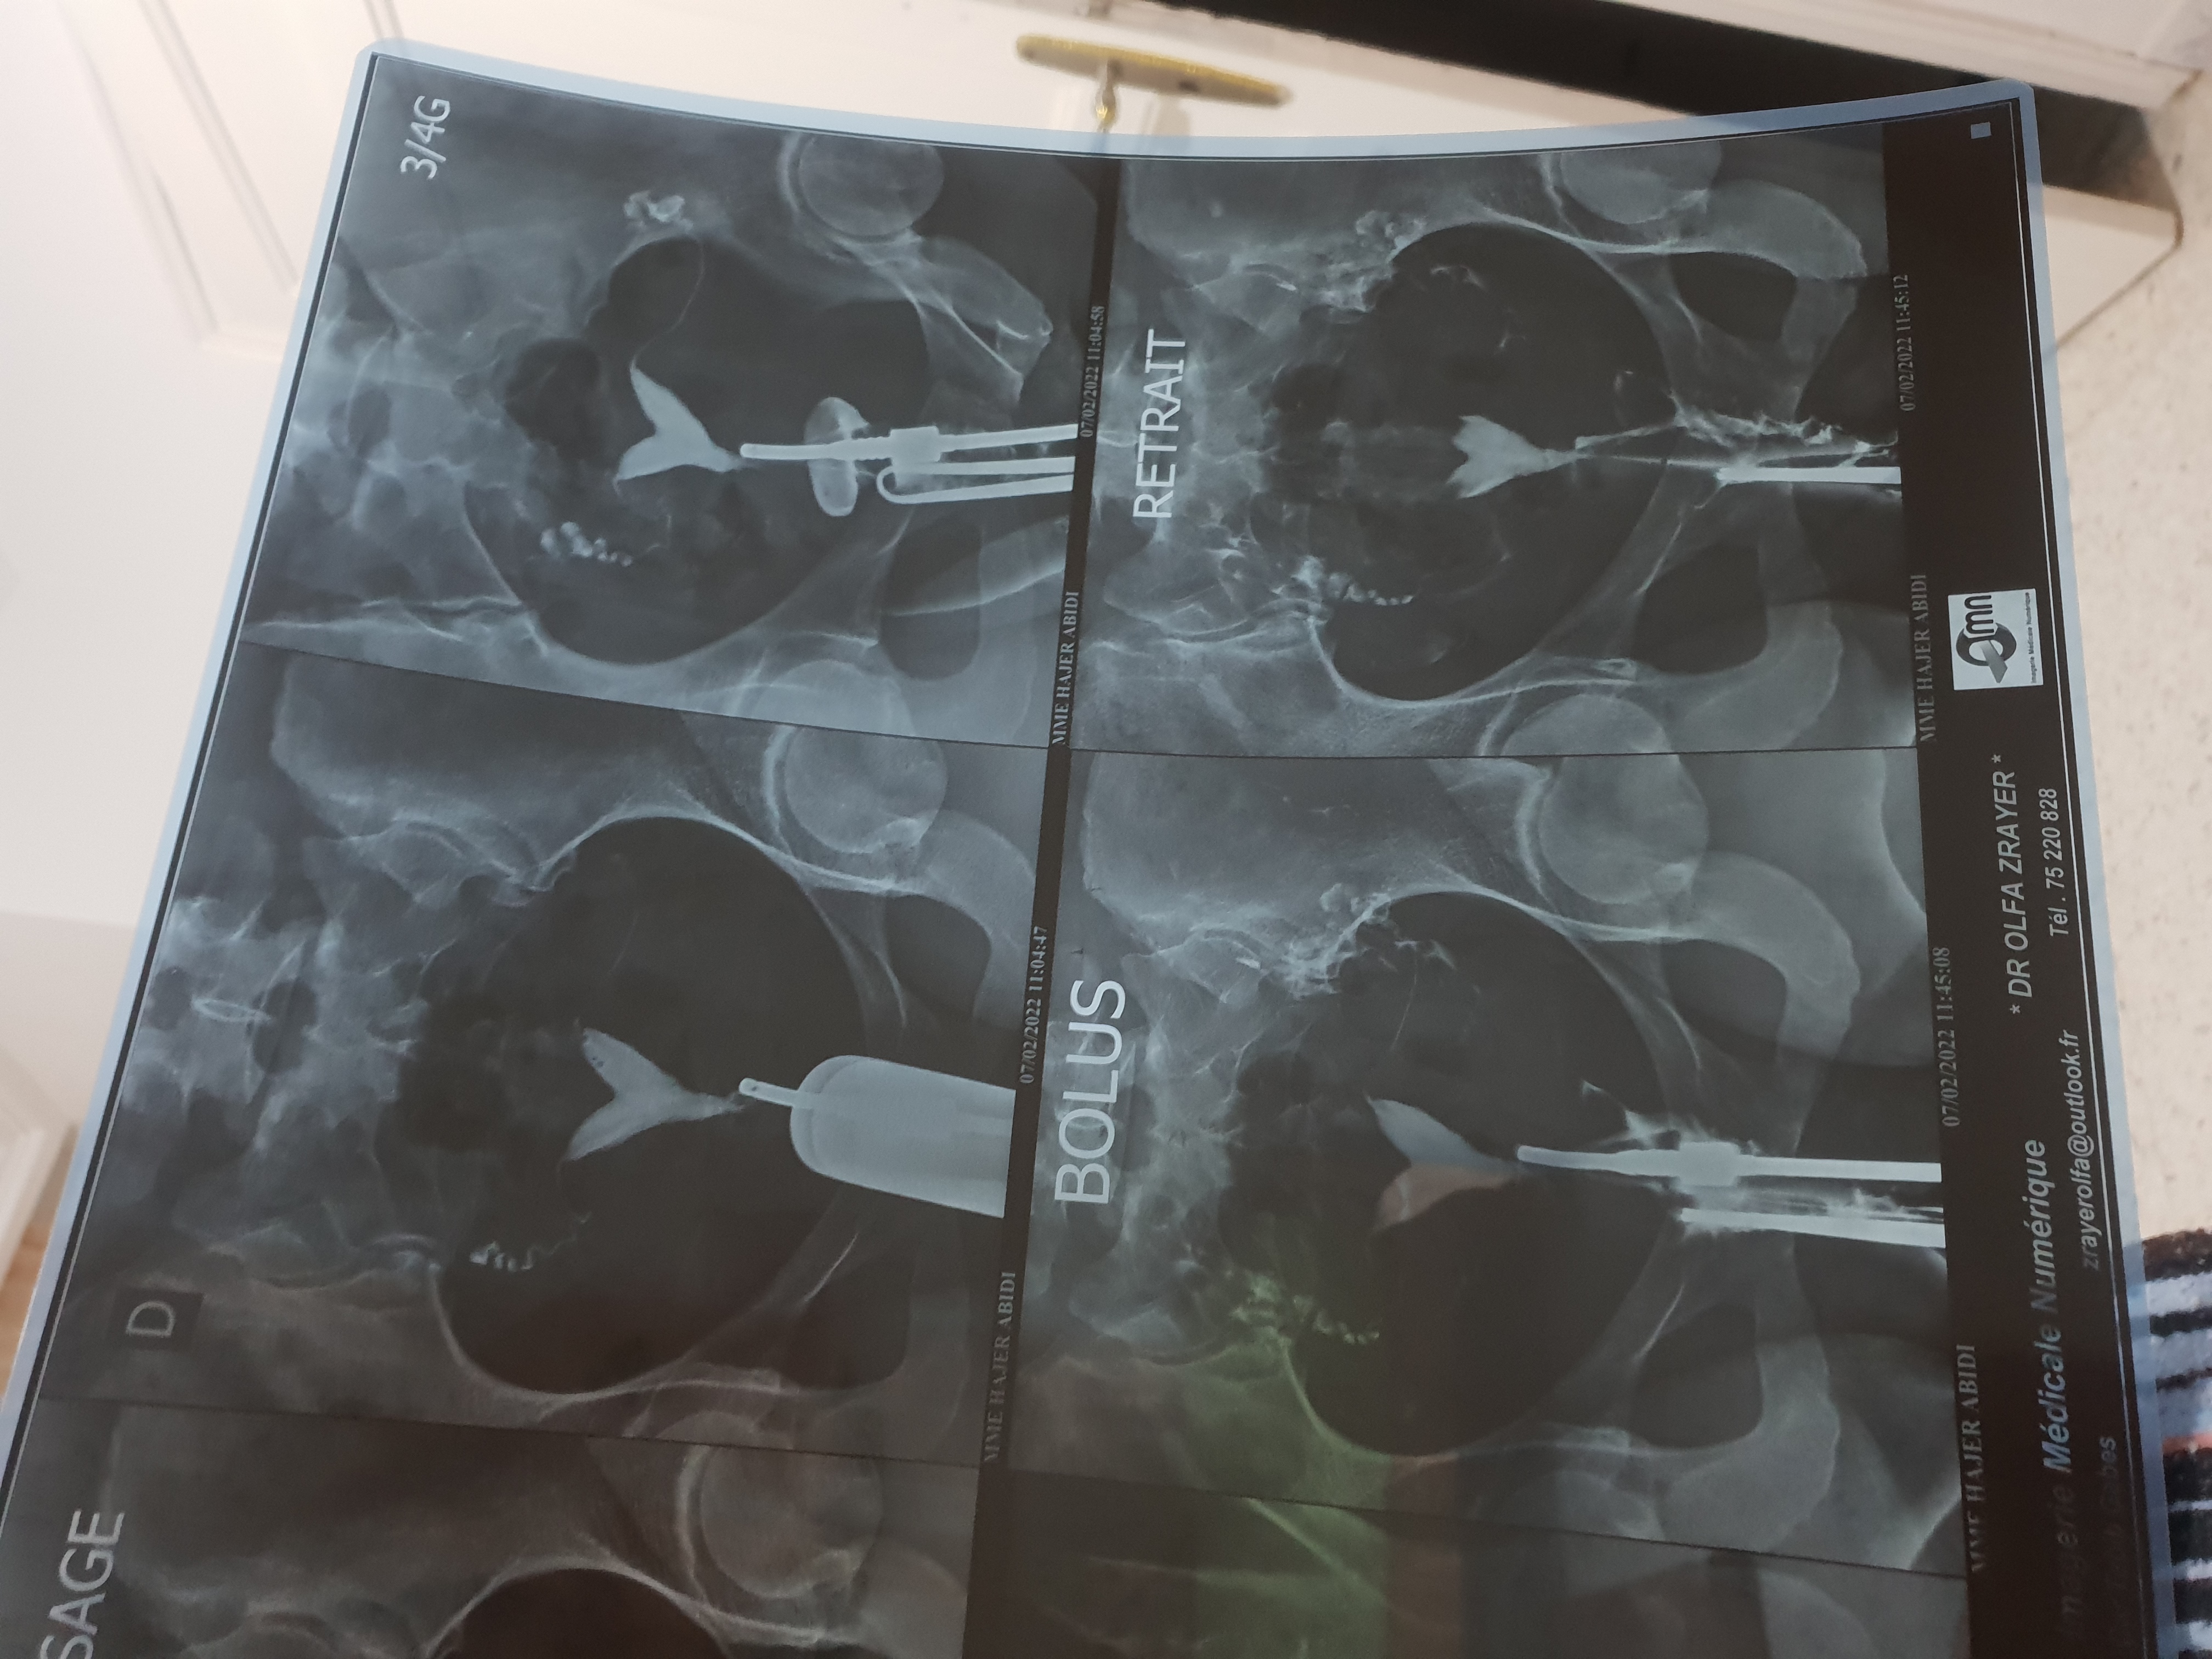

عملت كل الفحصوات والتحاليل كلها جيدة عملت صورة ضليلة للرحم من سنة كانت في انسدا وفتح اثناء الصبغة حدث حنل...

3 سنين زواج لم أحمل عملت تحاليل طلعت جيدة وعملت اشعة الصبغة الدكتورة قالت قناة فالوب مسدودة ودكتور ثاني قال...

متزوجة منذ ثلاث سنوات ولم يحدث حمل اشعة الصبغة جيدة تحاليل هرمونات جيدة مخزون مبيض ضعيف هل يمكن حدوث حمل...

عملت صورة ظليليةووجود انه القنوات مغلقة وتقوس بسيط بالرحم فطلب اجراء تنظير للرحم محاولة فتح الانابيب وازالةالتقوس فهل يوجد خطورة...